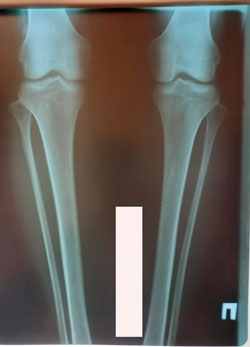

Исходник - 25 лет.

Дата операции - 16.12.2020

00.jpg